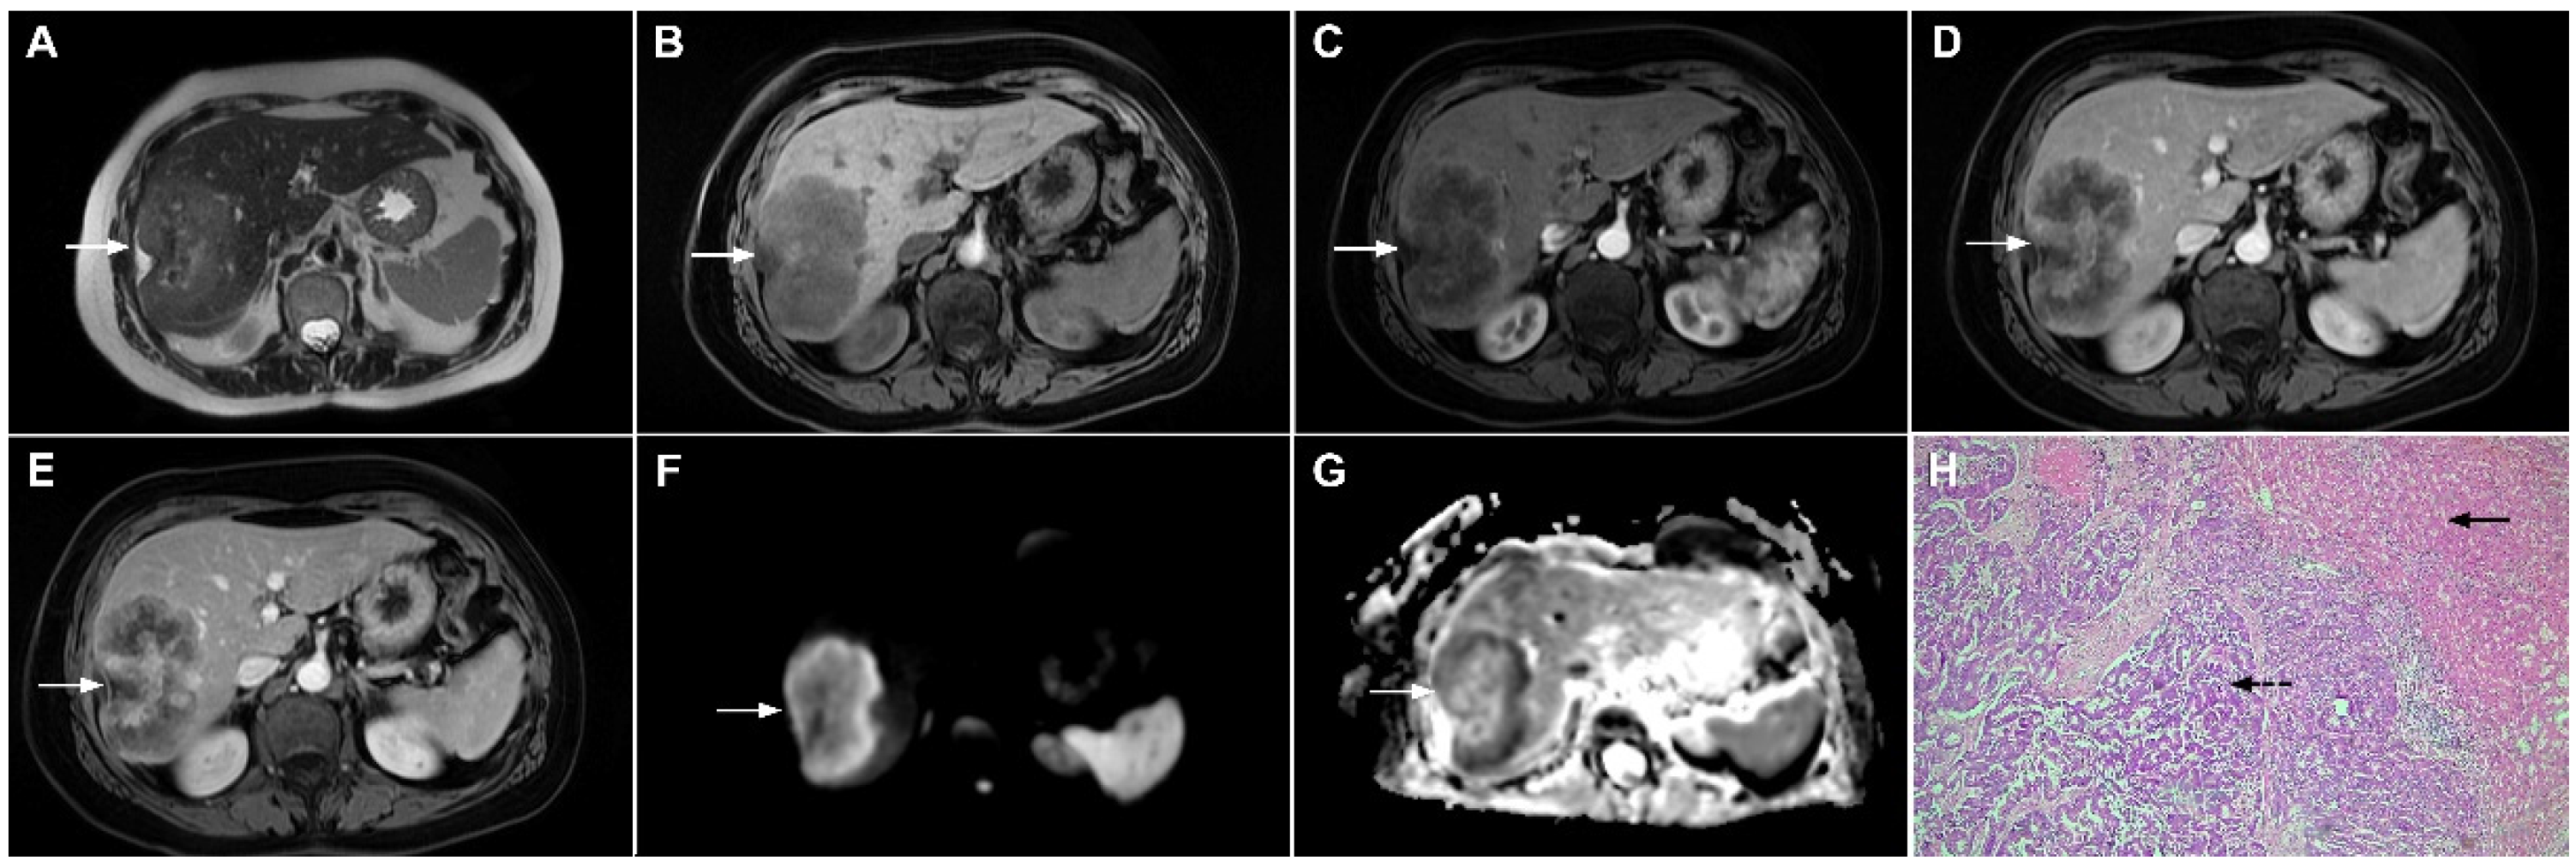

HEH may be of three different pathological types: single nodular, multifocal nodular, and diffuse type. The most common presentation is in the form of multiple, subcapsular nodes located in lesions that coalesce during the course of the disease [100]. Although multifocal nodular and diffuse types of HEH show characteristic radiological findings such as subcapsular localization, capsular retraction, and targetoid appearance on postcontrast study, the diagnosis of solitary HEH represents a diagnostic challenge [102]. Solitary lesion is the least frequent type of HEH and may closely resemble mICC [103]. Both lesions are heterogeneously hyperintense in T2-weighted images and hypointense in T1-weighted images [104]. With regard to tumor vascularity, Kim et al. have shown that solitary HEH usually shows minimal or rim-like enhancement in the early phase and delayed gradual fill-in, which is also a common vascular behavior of mICC (Figure 21). Moreover, both lesions may cause capsular retraction. In such difficult cases, the presence of the “lollipop sign” may suggest HEH [105]. This occurs when a well-defined liver nodule directly invades the vascular structure, resulting in its cut-off, which all together resembles the lollipop [105]. Furthermore, epidemiological data such as higher incidence in middle-aged females and normal values of CA 19-9 might be helpful in differential diagnosis, suggesting HEH [102]. On the other hand, if biliary dilatation is present adjacent to the tumor, the diagnosis of mICC is probable. The use of hepatobiliary contrast agents might be helpful in distinguishing between HEH and mICC, since mICC may show cloud-like appearance with central hyperintensity and peripheral hypointensity in the hepatobiliary phase, while it is rarely seen in HEH [102]. From the standpoint of treatment, the gold standard is radical surgical resection for both mICC and solitary HEH, thus preoperative differential diagnosis is not always necessary.

Figure 21.

Hepatic hemangioendothelioma in a 44-year-old woman. The axial T2-weighted FS image (A) shows a heterogeneously hyperintense lesion (arrow) in liver segment VII, which is causing a slight capsular retraction. In the plain T1-weighted image (B), the tumor is hypointense. Another smaller lesion is also seen in liver segment II (dashed arrow). After administration of intravenous contrast media, there is only subtle perilesional enhancement in the arterial phase (C) with a gradual centripetal enhancement in the portal venous (D) and delayed phases (E). The tumor (arrow) shows high signal intensity in the DWI (F) with low ADC values on the periphery in the corresponding ADC map (G). Hematoxylin and eosin (H&E) staining showed epithelioid hemangioendothelioma (arrows). Normal liver parenchyma is also shown (dashed arrow); original magnification ×40 (H).